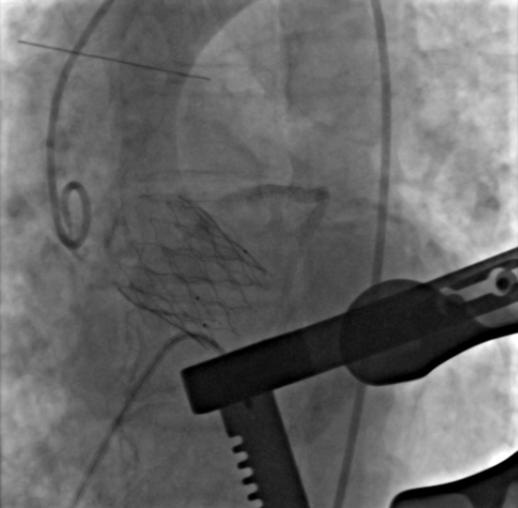

即刻造影